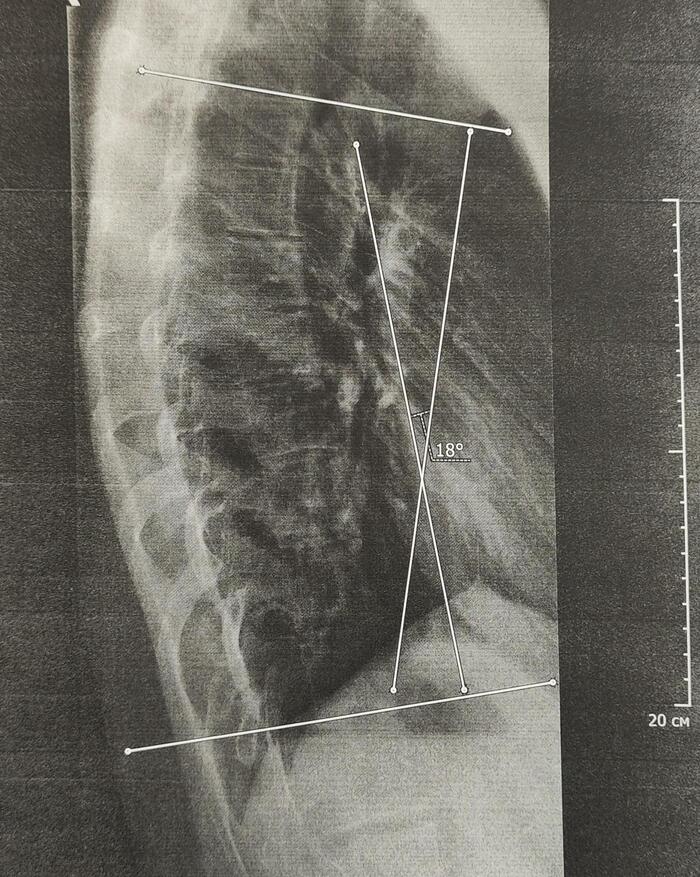

На Р-граммах грудного, поясничного отделов позвоночника определяется S -образное искривление оси позвоночника, с левосторонней дугой, вершиной на Th10,угол девиации 20 град., правосторонней дугой, вершиной на L2, углом девиации 15 град.

Итоговый диагноз: Патологический гиперкифоз грудного отдела позвоночника 4 ст. по Коббу. Клиновидная деформация тел Th6, Th7, Th8 позвонков, как следствие перенесенной остеохондропатии, соответствует болезни Шейермана-Мау.S-образный сколиоз 2ст.Остеохондроз грудного, поясничного отделов позвоночника.

В данном случае непризывные категории годности будут по сколиозу 2 ст(угол искривления более 18 град.)-ст.66в-В(ограниченно годен к в/сл), гиперкифозу грудного отдела позвоночника 4 ст, с клиновидной деформацией 3х позвонков грудного отдела как следствие остеохондропатии-ст.66а-Д(не годен к в/сл),иногда ставится 66в-В.